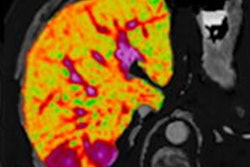

The study by Velicia Bachtiar, PhD, and colleagues, published on 10 April in PLOS One, demonstrated the technical performance of LiverMultiScan for measuring three key biomarkers of liver disease: iron, fibro-inflammation, and fat, according to the firm.

The researchers from Perspectum, the University of Oxford in the U.K., and the University of Westminster in London found that multiparametric MRI was a repeatable and reproducible method for quantifying liver tissue characteristics, even across equipment from different vendors and at different field strengths.